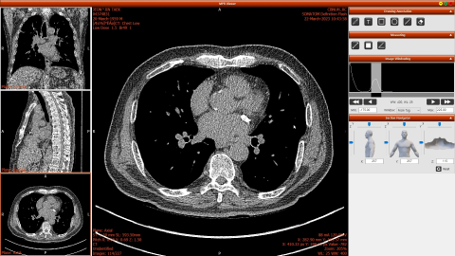

HEXA Pro는 인공지능(AI) 기반 흉부 CT 영상을 자동 분석해 폐, 심장, 간, 갑상선, 유방, 척추 등 주요 장기의 이상 질환을 동시에 탐지하는 차세대 의료영상 솔루션이다.

한 번의 CT 촬영만으로 6개 주요 장기를 분석하며, AI가 병변을 색상으로 표시해 이상 부위를 직관적으로 확인할 수 있다.

분석 결과는 전자문서 리포트(PDF)와 3D 이미지 형태로 제공되어 의료진이 환자의 상태를 한눈에 파악할 수 있으며, PACS 시스템과 연동되어 진료 현장에서 즉시 활용할 수 있다.